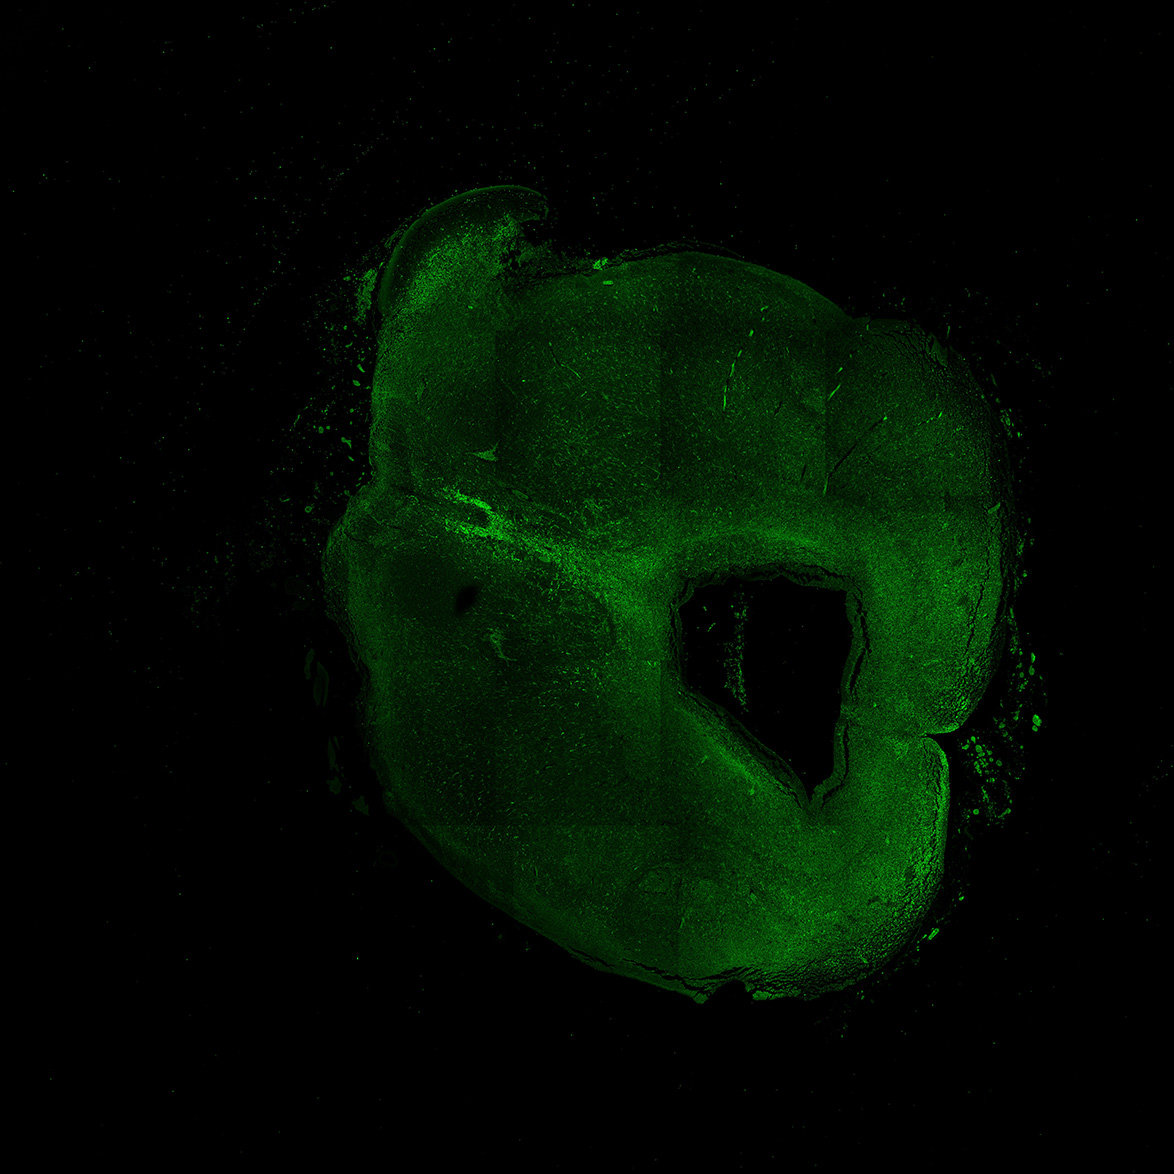

An anatomical analysis of the developing human midbrain from 6 post-conceptional weeks (PCW) to 22 PCW reveals increased tissue complexity, characterized by the emergence of dopaminergic nuclei, as highlighted by immunofluorescence analysis for tyrosine hydroxylase (TH).

11PCW

DAPI

11PCW human midbrain

MAP2

SOX2

Merged

TH